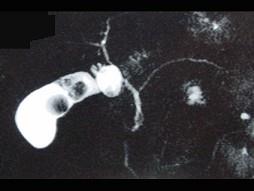

问题 男,51岁,右上腹痛,Murphy征阳性,皮肤、巩膜无黄染,影像检查如图,最可能的诊断是 ( )

选项 A.胆囊癌 B.胆囊息肉 C.胆囊结石 D.胆囊腺肌增生症 E.慢性胆囊炎

答案 C